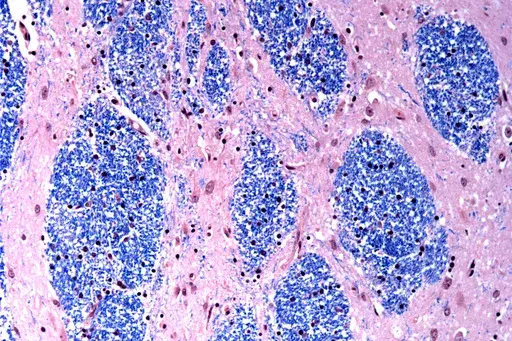

Scientists at the Broad Institute of MIT and Harvard, McLean Hospital in Massachusetts and Harvard Medical School studied brain tissue donated by 53 people with Huntington’s and 50 without it, analyzing half a million cells.

They focused on the Huntington’s mutation, which involves a stretch of DNA in a particular gene where a three-letter sequence – CAG – is repeated at least 40 times. In people without the disease this sequence is repeated just 15 to 35 times. They discovered that DNA tracts with 40 or more such “repeats” expand over time until they are hundreds of CAGs long. Once CAGs reach a threshold of about 150, certain types of neurons sicken and die.